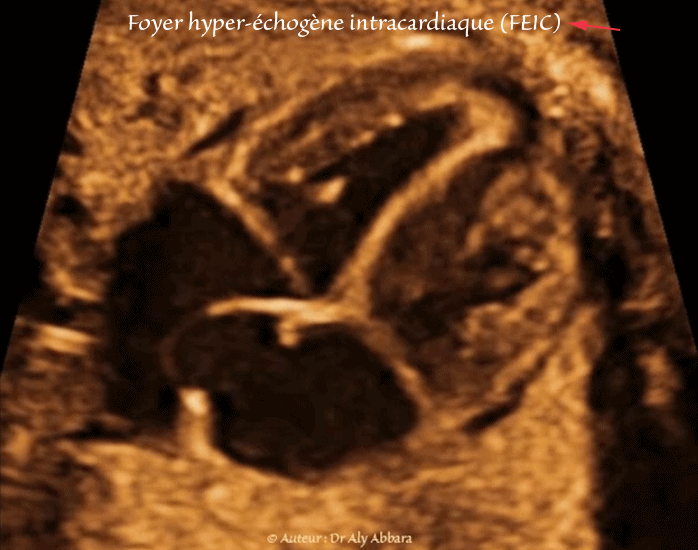

• Images échographiques montrant la présence, dans le ventricule gauche fœtal, un foyer hyperéchogène (spot ou point lumineux - echogenic cardiac focus -ECF ; intracardiac echogenic focus - IEF)

• Le spot intraventriculaire est un foyer ou nodule hyperéchogène (d'une échogénicité égale à celle de l'os) ; il s'agit d'une calcification (minéralisation) du muscle papillaire et d'un pilier valvulaire ; sa taille est habituellement inférieure à 3 millimètre.

• dans le ventricule gauche dans 78 % des cas ;

• dans le ventricule droit dans 18 % et ;

• bilatéral dans 4 % des cas.

• Le spot intracardiaque peut être unique ou multiple.

• Dans le cas étudié dans cet article, le fœtus est âgé de 33 SA et 4 jours, ne présente aucune d'anomalie significative morphologique, biométrique avec naissance à terme sans trouble de développement.